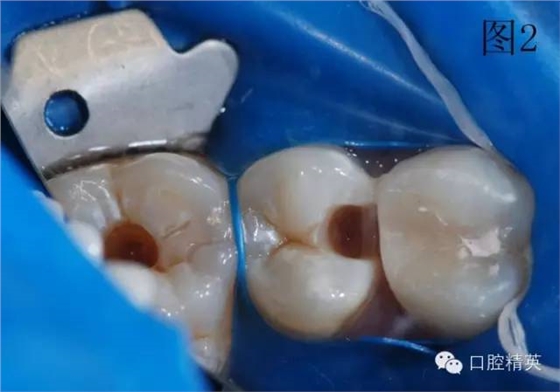

圖2、3為左上第一前磨牙充填結(jié)束,上橡皮障,充填另外兩顆牙。使用橡皮障,可以嚴(yán)密隔濕,防止樹脂受到污染,增加樹脂與牙齒之間的粘結(jié)力,延長充填物的使用壽命。

3顆牙充填完畢,卸下橡皮障夾和障布。